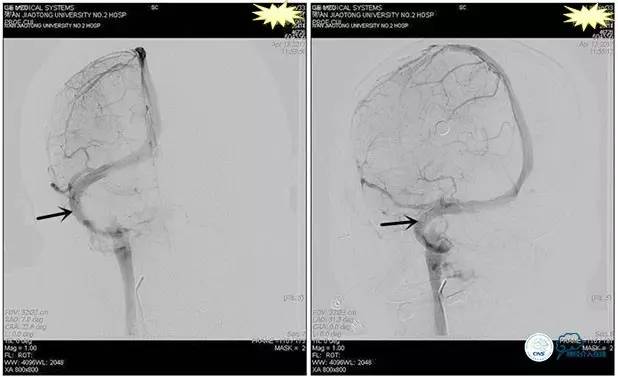

诊疗方案:为挽救视力,确定支架成形术效果,急诊行右侧横窦乙状窦狭窄球囊扩张术(6mm×20mm,Ever Cross )。

术中测压

远端压力:530mmH2O

近端压力:120mmH2O

术中造影

术后造影

狭窄较前有改善